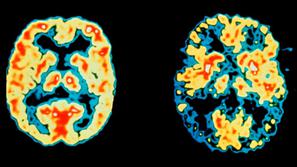

Normalni možgani in možgani bolnika z Alzheimerjevo boleznijo

Zdravje

Slovenci sodelujejo pri prizkušanju novih zdravil

Znanstveniki so odkrili učinkovini za Alzheimerjevo bolezen, ki bi lahko učinkovito vplivali na potek te doslej neozdra…